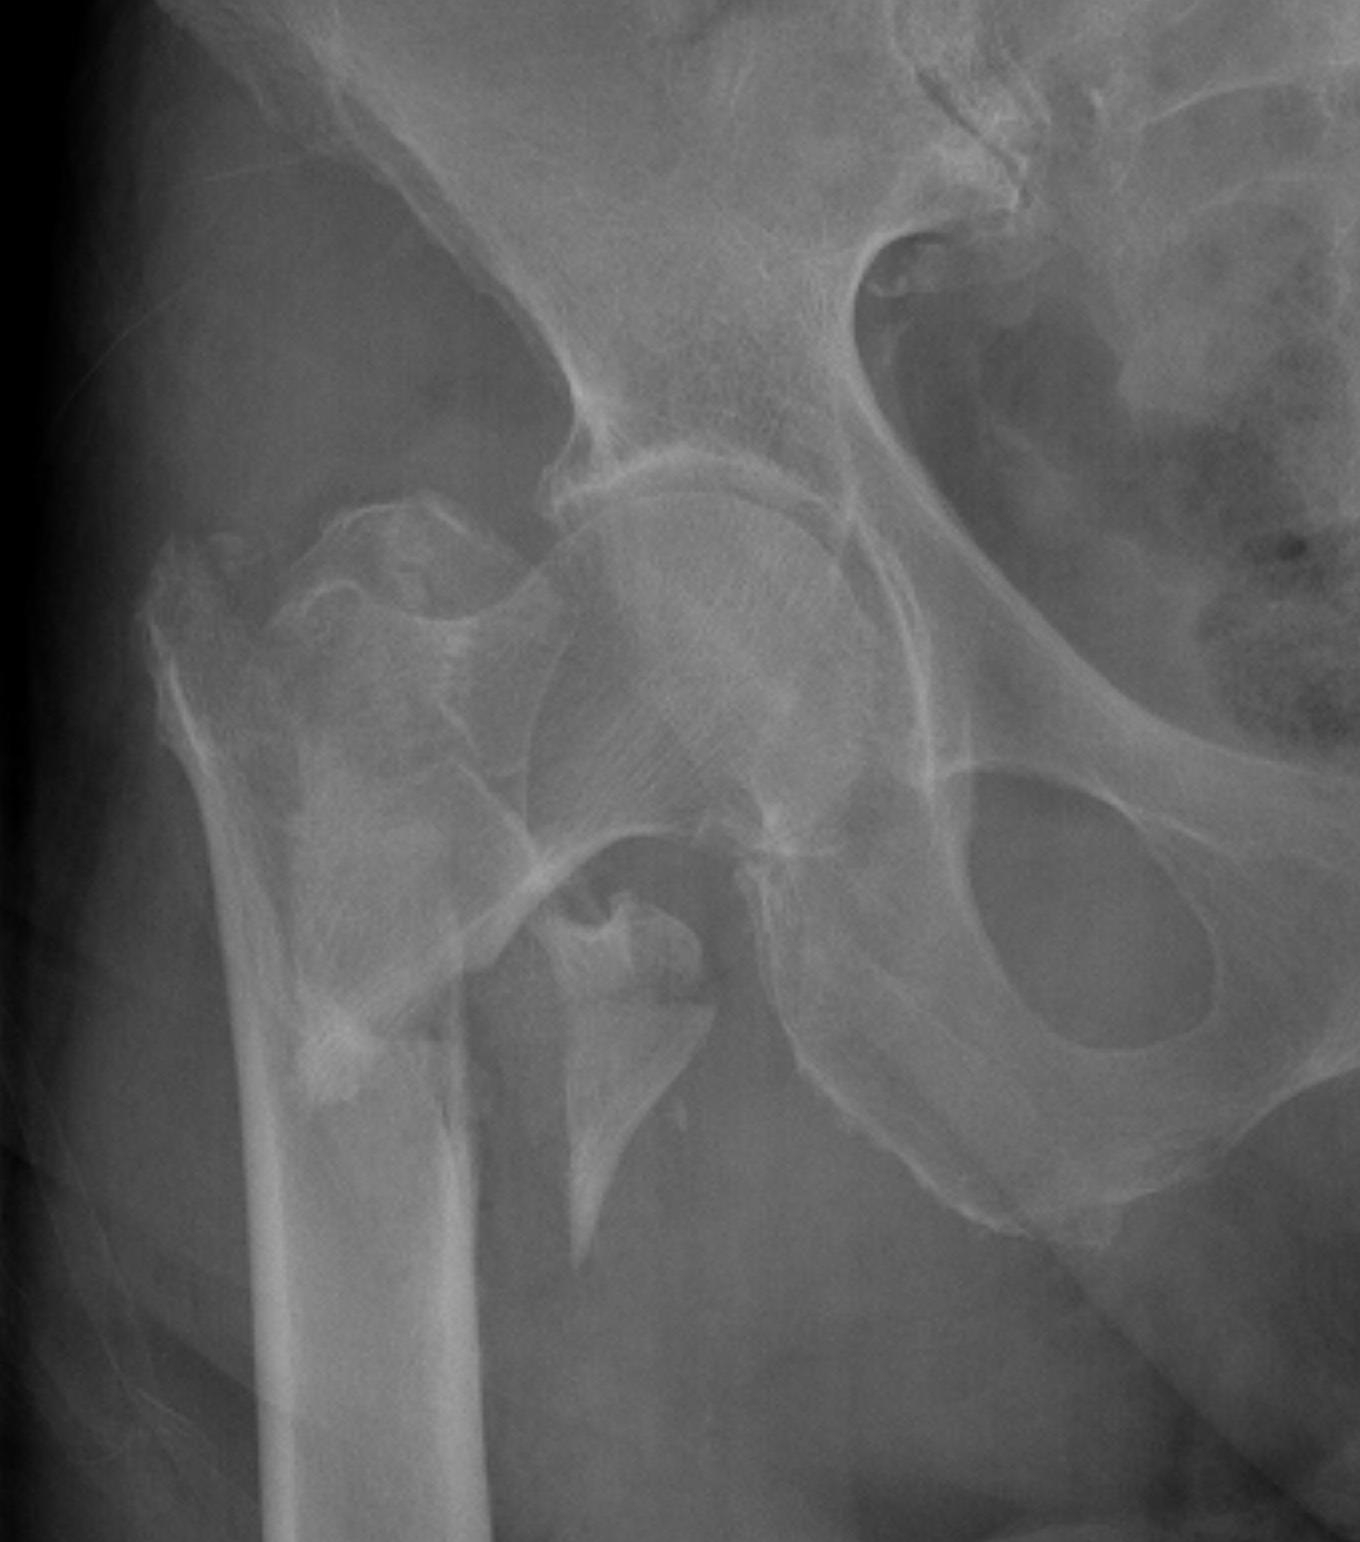

Complications

Malreduction

Screw cut out

Malunion

Non union

Screw Cut

Causes

- malreduction

- poor screw position / high tip apex distance

- poor bone quality

Excessive lateral sliding / shaft medialisation

Cause

- collapse with insufficent lateral buttress

- reverse obliquity fracture